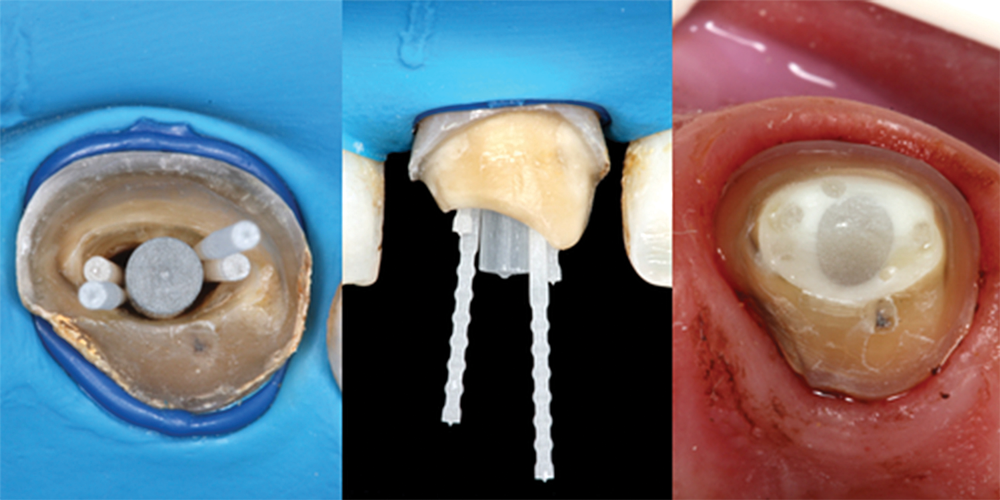

(6.) Occlusal and buccal views showing placement of accessory posts and occlusal view of the completed buildup.

Figure 6